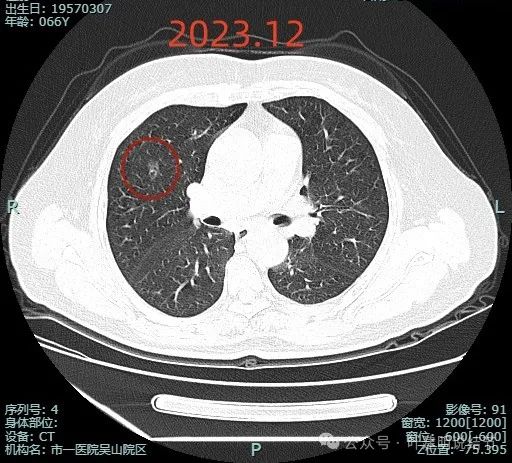

先来看病灶较大层面不同时期的影像:

这是患者在市一医院吴山院区检查后的2023年12月时的影像,右上叶磨玻璃密度结节,轮廓较清,密度似乎不是非常淡,表面显毛糙。